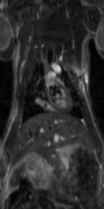

ラット心臓・脳脊髄液のシネ画像

トリガーからパルス起動までの時間を変化させ、それを編集することで心臓が動いているようなシネ画像を撮ることもできます。

Perfusion 画像

腎臓の血流評価